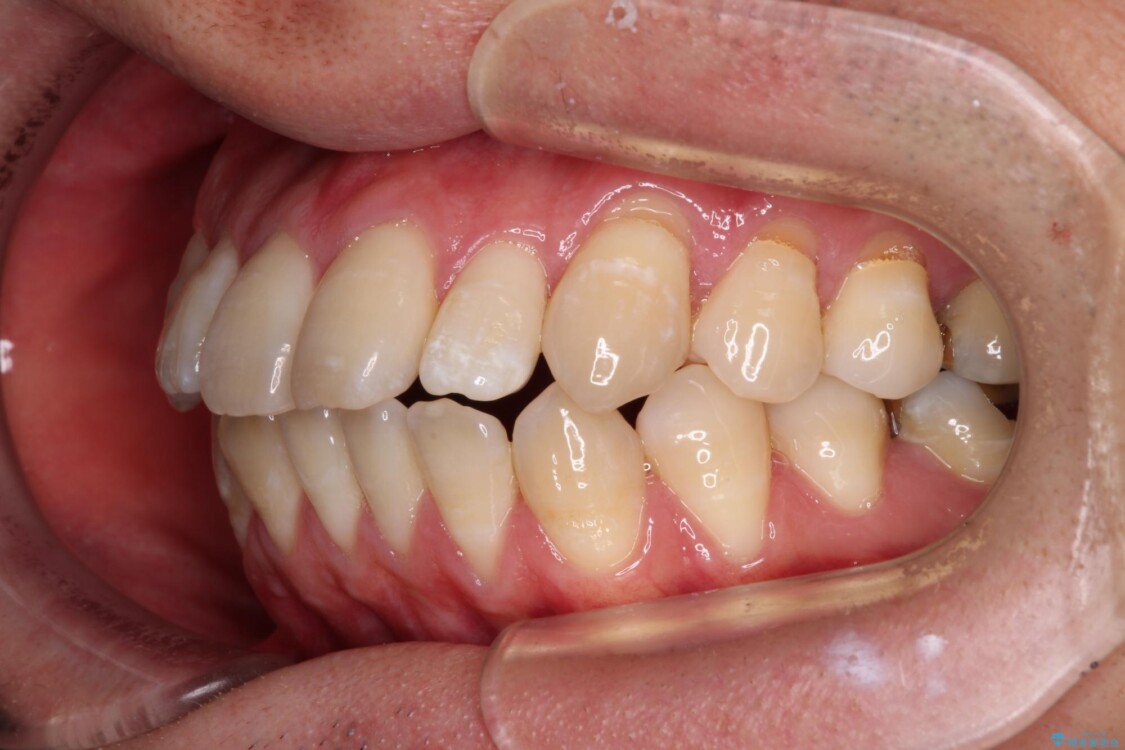

治療前

• 口元の突出感を改善!目立ちにくいワイヤー矯正で自信を持てる自然な横顔に 治療前画像

「横から見ると唇が前に出て見えるのが気になる…」 「マスクを外すのが恥ずかしい…」 そんな口元の突出感に悩まれてご来院された患者様。

精密検査の結果、上下左右の小臼歯4本を抜歯し、そのスペースに前歯を後方へ移動させる矯正治療をご提案しました。